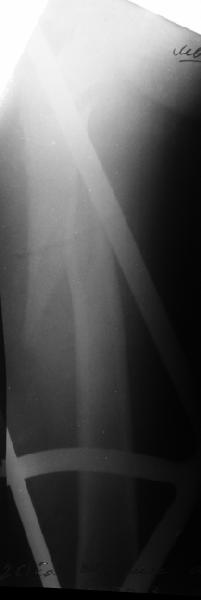

Как раз недавно у меня был примерный случай: больному 36 лет, поступил ночью, травма в результате мотоциклетной аварии, кроме чрезвертельного и спирального перелома левого бедра имеется переломы костей предплечья с этой же стороны. Скелетное вытяжение, а на следующий день больной про оперирован на ортопедическом столе с дистракцией. Чтобы не расколоть чрезвертельный перелом провели временную спицу ближе к переднему кортексу, из малого разреза костодержатель для репозиции, а фиксацию провели антиградным штифтом. Этапы операции на снимках.

Да, сейчас это и у нас самый напрашивающийся выбор. Сделали гвоздем ChM, картинки в приложении.